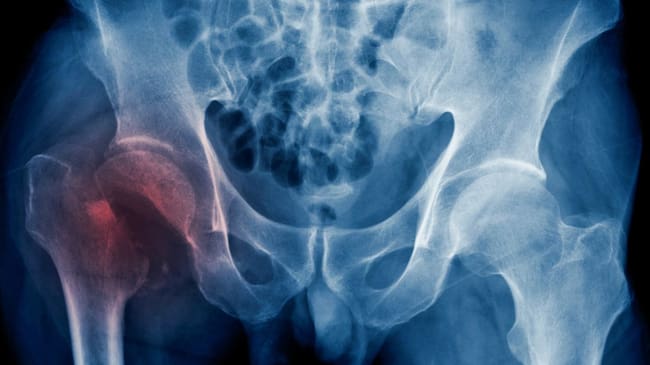

Solo el 50% de las fracturas de cadera se operan antes de las 48 horas

La cirugía tardía se asocia a un incremento en el número de muertes según las principales guías de práctica clínica. La mortalidad hospitalaria por este motivo en la Comunidad de Madrid es del 6,27%, dos puntos por encima de la media nacional

Los datos los publica el Observatorio de Resultados de los hospitales del Servicio Madrileño de Salud. Durante el año 2017 'el porcentaje de episodios con fractura de cadera intervenidos en las primeras 48 horas fue de 52%'. La mortalidad hospitalaria por este motivo en la Comunidad de Madrid es del 6,27%, dos puntos por encima de la media nacional y casi cuatro puntos por encima de la ciudad de Lugo.

El 52% de fracturas de cadera operadas antes de dos días es una media de los veintiséis hospitales públicos que realizan este tipo de cirugía, pero los hay que empeoran esta cifra: El Ramón Cajal, el 12 de Octubre y el Gregorio Marañón no llegan al 40%.

El peor de todos los hospitales, el que tiene la cifra más baja, es el Ramón y Cajal. En este centro sólo tres de cada diez pacientes que ingresan en este centro con fractura de cadera son operados antes de las 48 horas. A parte del aumento de la mortalidad, la cirugía tardía se asocia también con un incremento de las infecciones, las ulceras por presión y otras complicaciones médicas.

Son muchas las patologías que, según Veloso, se pueden evitar a los pacientes con se se les opera antes de dos días desde que se produce la fractura: "Según los últimos estudios científicos los pacientes que se sometieron a una cirugía en un plazo de 24 horas tenían un 82% menos de posibilidades de desarrollar una trombosis venosa profunda en las piernas, un 61% menos de posibilidades de tener un ataque cardíaco y un 49% menos de probabilidades de sufrir una embolia pulmonar."

En los hospitales del Servicio Madrileño de Salud se atendieron durante el año 2017 un total de 5.597 episodios de fractura de cadera con una mortalidad hospitalaria del 6,27%. La media en España es del 4,3%.